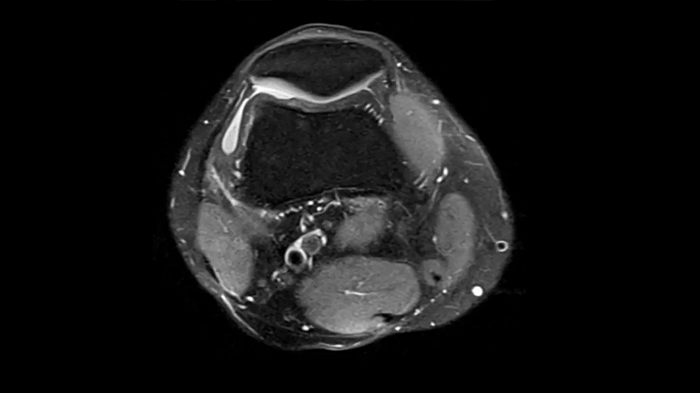

3D MSK Imaging with Compressed Sensing

Knee imaging with T2w SPACE can be expedited using Compressed Sensing to reduce acquisition times, offering high-resolution images for uncompromised knee assessments.

Compressed Sensing 6

0.3 x 0.3 x 0.6 mm2

TA 4:15 minutes

MAC-ID: 7aaaa0175.

MAC-ID: 7aaaa0175. Image Credit: Siemens Healthineers